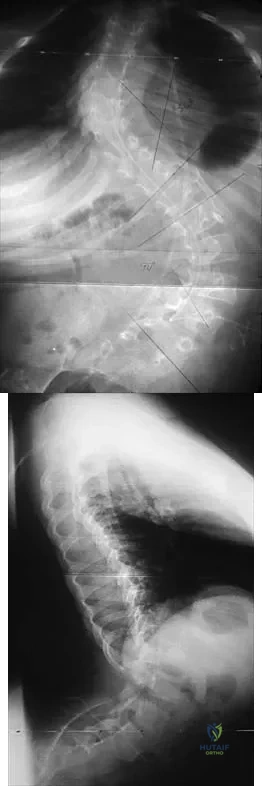

Figures 21a and 21b show the radiographs of a 12-year-old patient with an L4-level myelomeningocele who has scoliosis that has been slowly progressing for the past several years. There has been no loss of motor function. An MRI scan shows no syringomyelia or increased hydrocephalus. Management should consist of

Explanation